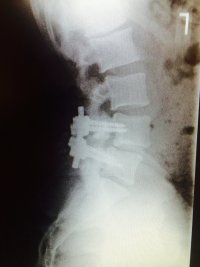

had spinal fusion surgery January 2014, just went back to doc today because I'm now having nerve pain again. two of the four titanium screws broke. bone moved back to hitting my sciatic nerve. he tells me he doesn't want to do another surgery because it's too invasive and he'd have to go through my side instead of the back to get to spine to put in new hardware with a cage and shit. he wanted to refer me to a pain management doc and take pain pills the rest of my life. I said no way. getting a second opinion.

before

ImageUploadedByTapatalk1405657440.992933.jpg

after

ImageUploadedByTapatalk1405657464.944480.jpg

View attachment 54553

View attachment 54554

Damn bro L4 slid anterior and L5 slid posterior, yeah I know you are having nerve pain for sure my man. Sorry brother